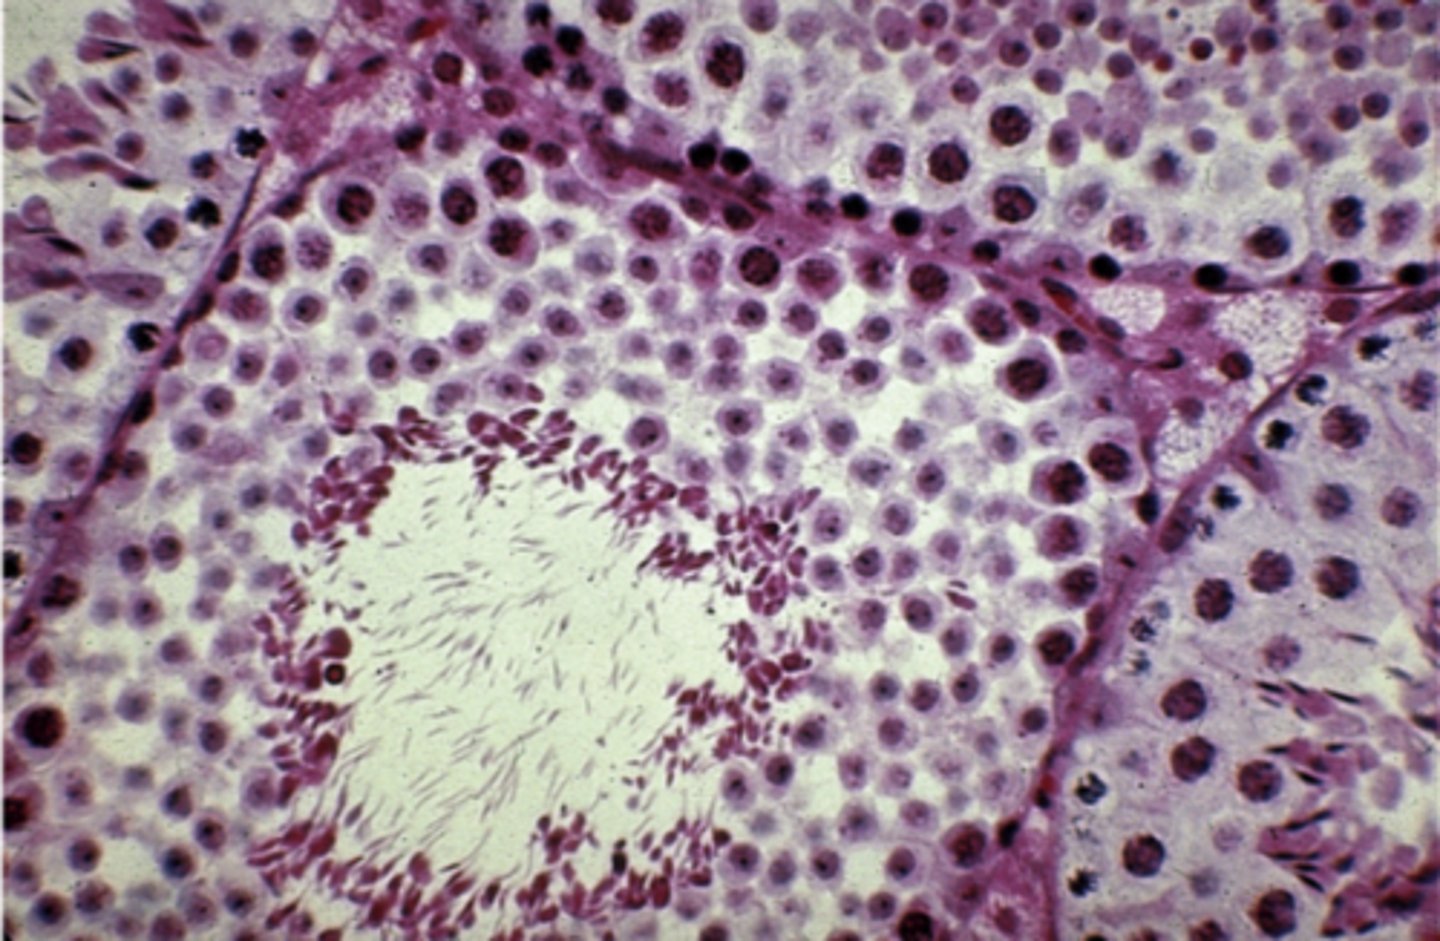

Epididymis

What is this?